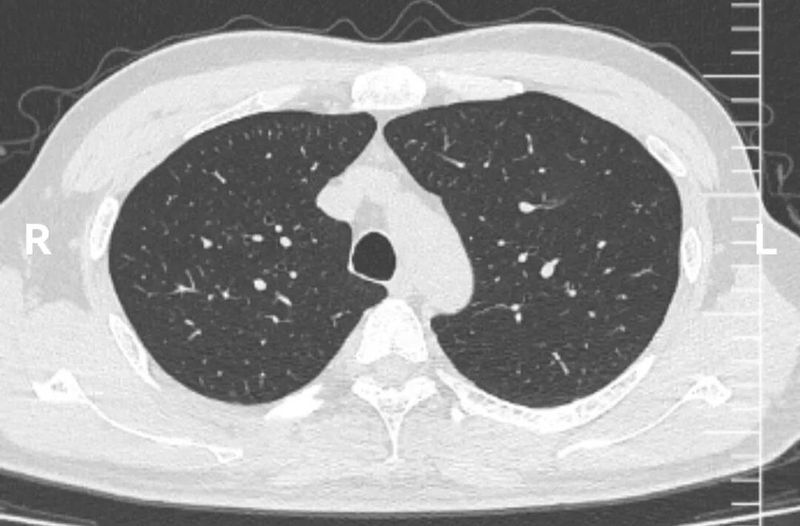

CT图像

这个左上肺混杂磨玻璃结节CT图像非常有特点,首先,磨玻璃成分为主,而且磨玻璃成分边界模糊不清。这本身就是炎症的典型表现。其次,实性成分的形态边界比较清楚,没有分叶、血管异常等形态。